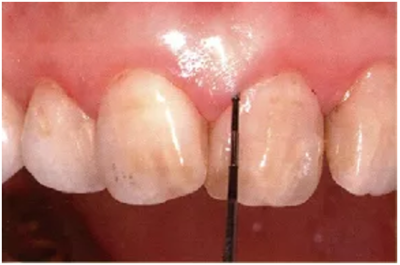

2、探針的插入

頰側(cè)、舌側(cè)的測定

探針要與牙軸平行插入。注意不要探針的尖端離開牙面。

舌側(cè)數(shù)值難以讀取,要學(xué)會利用口鏡來讀取。

● 頰側(cè)、舌側(cè)探針的插入

通常與牙軸平行插入

舌側(cè)難以看到的位置就利用好口鏡來輔助。

注意盡量讓探針貼著牙面。